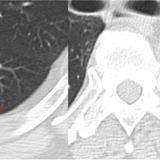

Rounded atelectasis case 1

Date: 01/13/2008

Views: 3481